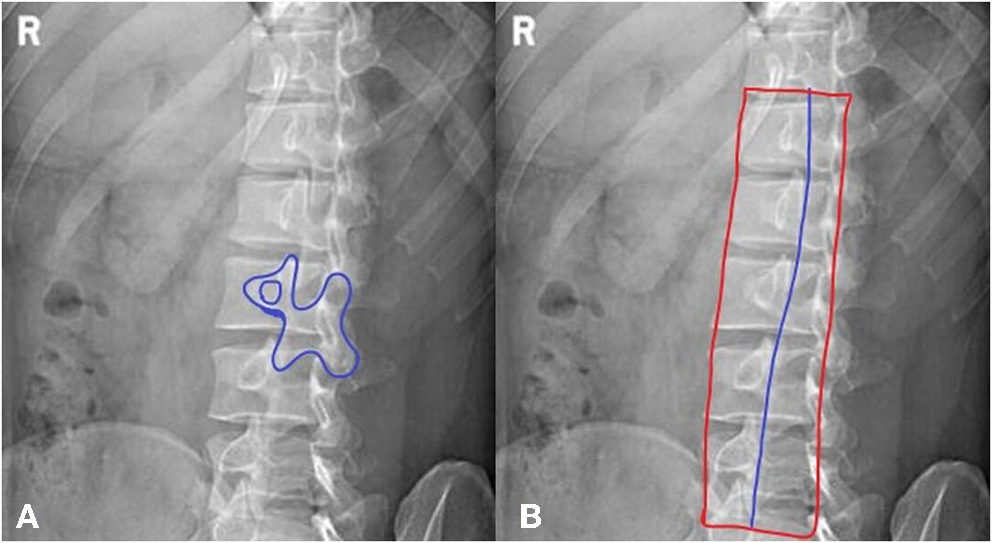

b. The “dog” sign is observed, showing the articular process and facet joints (as shown in Figure 1A).

Figure 1

A method for jugement of “Dog” sign. (A) The dog's mouth is for ipsilateral transverse process. The dog's eye is for pedicle. The dog's ear is for superior articular process. The dog's neck is for interarticularis. The dog's body is for lamina. The dog's front leg is for inferior articular process. The dog's tail is for contralateral transverse process. (B) The inferior articular processes were connected in blue line.

In the oblique view of the lumbar spine, as shown in Figure 1B, the inferior articular processes of the lumbar vertebrae, which form the shape of a dog, were connected into a line. Their average position in the whole vertebrae was calculated. All qualified images that had the “dog” characteristic were counted and a certain range was obtained.